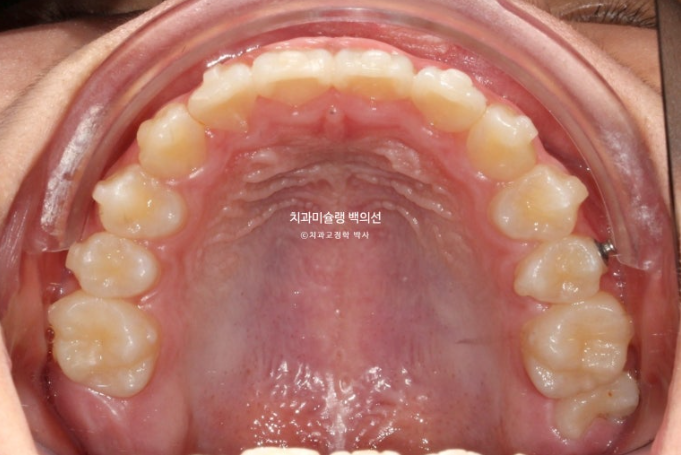

공간부족으로 인한 덧니가 심해 반대교합이 있습니다.

악궁확장을 통한 덧니배열을 목표로 인비절라인퍼스트 교정치료 권유드렸습니다.